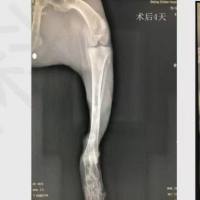

3.头颅CT检查:显示血肿位于额叶脑实质内 ,血肿呈混杂密度 ,血肿周围有明显水肿带 ,中线向对侧移位 ,显示明显的高颅压特点